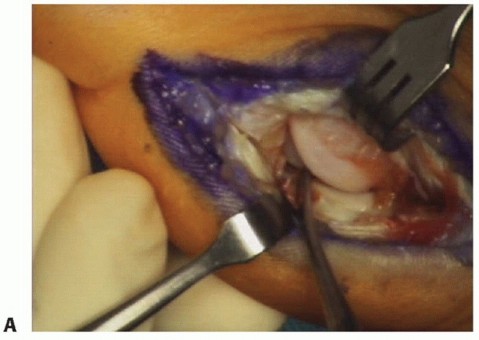

Described approaches include a plantar-medial, medial and plantar-lateral, and the J configuration. Over the past 6 years, we have employed the combined medial and plantarlateral approach in patients suspected of having a complete plantar plate disruption. This approach allows for a more direct repair of the lateral structures without extensive skin and neurovascular dissection and retraction. Improved wound healing has been noted anecdotally (FIG 7).

FIG 7 • Intraoperative photograph of the medial (A) and plantar-lateral (B) incisions about the hallux MP joint used for exposure and repair of the plantar plate rupture.

In this example, the surgeon has elected to use the J incision, which extends plantar medial and then

crosses plantarly along the flexor crease at the base of the phalanx (TECH FIG 1A). Take extreme care to identify and protect the plantar-medial digital nerve (TECH FIG 1B).

Make a longitudinal incision at the level of the abductor hallucis tendon (TECH FIG 1C). This allows both intra- and extraarticular examination of the plantar complex.

Fully define the extent of the injury (TECH FIG 1D).